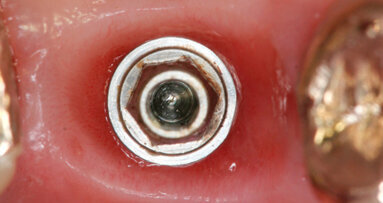

Il nostro obiettivo è quello di riuscire a dare alla paziente un provvisorio immediato nell’arco di due ore. Questo diventa possibile perché abbiamo utilizzato un flusso digitale fin dall’inizio. In laboratorio vengono realizzate la dima chirurgica (Figg. 16, 17), la dima protesica (Fig. 18) e anche il provvisorio (Figg. 19-21) che contiene delle alette di riposizionamento. Il tutto gestito con modelli digitali sui quali saremo in grado di funzionalizzare il provvisorio post-chirurgico (tecnica DIL). In un caso come questo se utilizziamo un flusso digitale possiamo evitare subito dopo la chirurgia di rilevare un’impronta degli impianti inseriti. Infatti, utilizziamo una dima chirurgica che ci faciliterà le fasi di intervento. La dima ci consentirà di non fare lembi e nessuna incisione di rilascio (Fig. 22), dopo aver inserito gli impianti (BLX Straumann) (Figg. 23-31) e aver controllato il loro alloggiamento, inseriamo sugli stessi dei transfert da impronta (Fig. 32).

Fig. 32 - Transfert avvitati sugli impianti.

Alloggiamo la dima protesica (Fig. 33), e blocchiamo i transfert con della resina trasparente (tecnica DIL) (Figg. 34, 35). In questo modo possiamo far riposare il paziente in studio dopo appena 35 minuti dall’inizio dell’intervento. La dima protesica, infatti (Fig. 36) con i transfert inseriti viene completata con l’unione degli analoghi ai transfert (Fig. 37). L’insieme così composto viene riadattato sul modello master digitale iniziale (Figg. 38-40) sul quale era stata costruita sia la dima chirurgica che la dima protesica come anche il provvisorio. Gli analoghi vengono bloccati sul modello con resina trasparente (Figg. 41-43). Alloggiamo il provvisorio sul modello master digitale così ottenuto (Figg. 44, 45).

Le fasi successive sono tecniche, uniamo la componente secondaria angolata a 17° programmata agli analoghi degli impianti (Figg. 46-49), su di essa avviteremo il moncone SRA (Figg. 50, 51). Alloggeremo il provvisorio sul modello (Fig. 52) e le alette di riposizionamento ci consentiranno di essere precisi. Unire il provvisorio alle componenti secondarie sarà a questo punto molto semplice con resina fotopolimerizzabile (Fig. 53). In poco più di un’ora abbiamo funzionalizzato il provvisorio (Figg. 54-57). Il montaggio del provvisorio avverrà collegando prima le componenti secondarie angolate agli impianti (Figg. 58, 59) e poi il provvisorio stesso (Figg. 60-70).

Fig. 58 - Alloggiamento SRA sul 1.2.

Fig. 59 - Alloggiamento SRA sul 2.2.